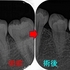

詰め物外してみたら歯冠破折だった。。。

歯が折れる場合はざっくり言って、

歯茎に埋まっている「根っこ」が折れる「歯根破折」と口の中で見える白い歯の部分が折れる「歯冠破折」があります。

「歯根破折」は抜歯になる場合が多いですが、やっている先生にかかれば接着修復という手もあります。

「歯冠破折」は頭の部分で割れだいたい骨の部分で止まるパターンが多いです。

歯冠破折.jpg

今回のケース 以前お母さんの治療をさせてもらった20代のお子さん

近医の先生に左下6に虫歯があると言われた。

レントゲン

2026 EEdental NNS (1).jpg

口腔内写真

2026 EEdental NNS (2).jpg

低目にレジンが詰めてあります。

患者さんには咬頭が無くなっており、中で虫歯もひろがっていそうだから

メタルアンレーで治しましょうと説明

治療を開始すると、「え!?」というぐらい詰め物が深い

歯茎の中のレジンも途中までしか詰めれておらず隙間から歯の中に歯茎が入り込んで来ている・・・

途中からこれ初発は虫歯ではなく歯冠破折で、長い期間で隙間から2次カリエスが出来たケースだと分かってきました。

歯の中の歯茎は電メスを使い除去

虫歯を削り終わると

2026 EEdental NNS (3).jpg

露髄した部分には第3象牙質が見られます。

エナメル質をなるべく残す為にEENOスフィアなどを使いくり抜くように虫歯を削っています。

ただ、こうなるとメタル修復するよりレジンで治した方が良いと判断し

患者さんとお母さんに理由を説明してレジン充填を行いました。

術前⇒術後

2026 EEdental NNS (5).jpg

2026 EEdental NNS (4).jpg

最後に咬合をチェックすると臼歯部に側方運動時のガイドがあり、

たぶん、昔もこのガイドが極端に強くて割れたんだろうなと推測。

2026 EEdental NNS (6).jpg

*最初の図と同じ割れ方になってました。

遠心にも似たようなガイドがあったので、最後に側方運動の咬合調整を行い終了となりました。

若い患者さんでも、夜間の歯ぎしりが大きい人はこのように歯冠破折を起こすことがあります。

先にも書いたように治し方が確立していないので、かかった歯科医院毎で治療法はことなりますが、

個人的には神経は残せれば大きく削らず処置したい所ではあります。